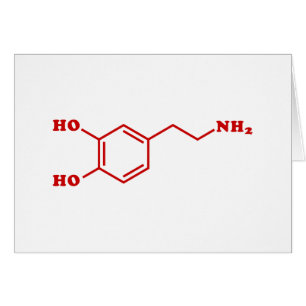

Dopamin Molecular Chemical Formula Greeting Card

Sale Preis 3,83 €. Originalpreis 5,46 €.